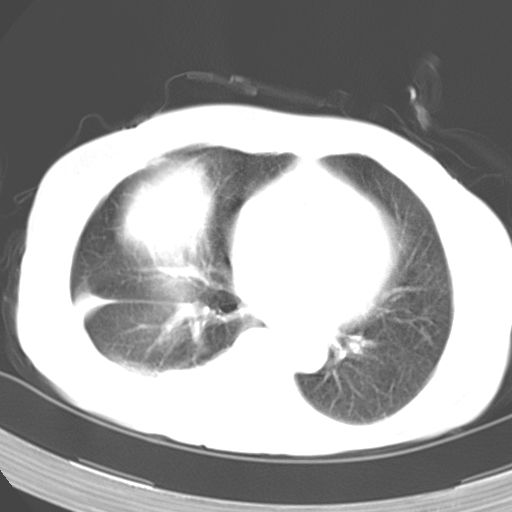

以下是引用dyqct在2006-12-7 21:08:00的发言:[br]考虑:1、肝内外胆管多发性结石伴肝左叶外侧段肝萎缩;[br] 2、右膈下多发脓肿;[br] 3、右侧少量胸腔积液、斜裂积液;[br] 4、左肾囊肿。

以下是引用jiazh在2006-12-7 20:37:00的发言:[br]肝脏周围半狐形低密度影,肝脏表面受压推移,考虑膈下脓肿可能性大;2、右侧胸腔积液

以下是引用拾荒者在2006-12-7 21:44:00的发言:[br]肝内外胆管多发结石,右膈下多发脓肿,右胸膜腔及叶间裂积液,左肾囊肿。[br] [br]